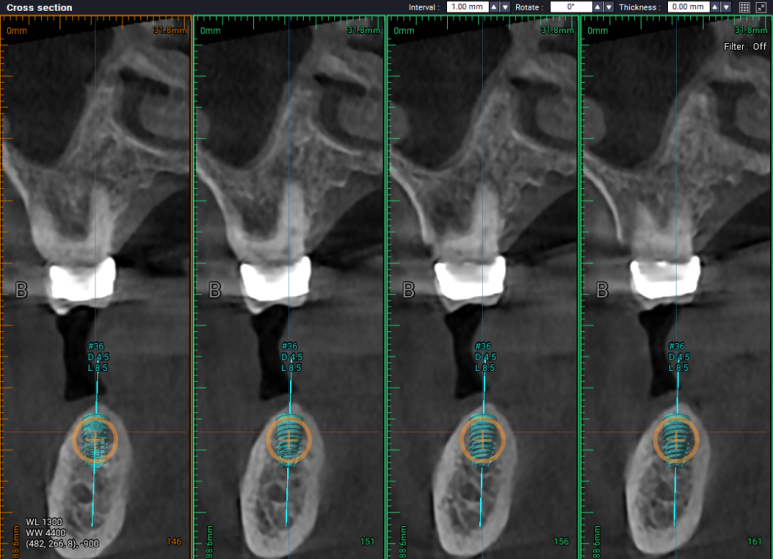

#34,36,37 자리에 임플란트를 식립할 예정이었어요.

#34번 부위는 임플란트를 위치시키고 나면 협측으로 뼈이식을 반드시 넉넉하게 해야할 모양새였습니다.

비교적 뽑은지 오래되었던 #36,37 치아는 잇몸뼈가 넉넉하게 보였습니다.

두 큰어금니 부위는 하치조신경관(아래이틀신경)만 조심해서 적절한 임플란트를 심어놓으면 되었습니다.